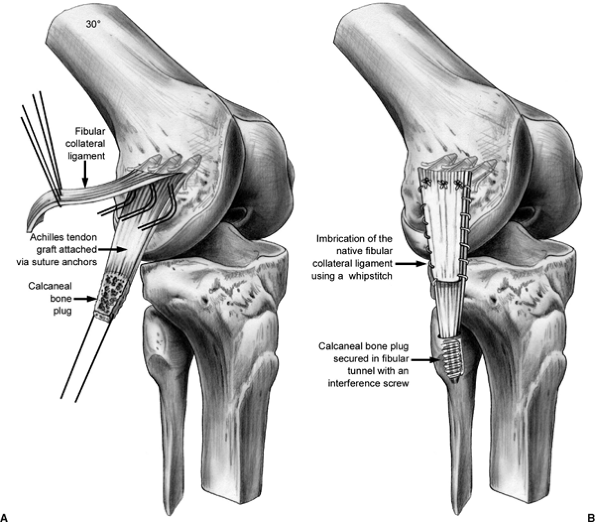

suture (Fig. 25.7). If reconstruction of the LCL is indicated, we prefer to use an

Achilles allograft, with imbrication of the native LCL by a whipstitch.

The tendinous portion of the allograft is secured to the LCL femoral

insertion via drill holes or suture anchors. The distal insertion of

the LCL on the fibula is dissected free, and a tunnel is drilled along

the longitudinal axis of the fibula. The calcaneal bone plug is secured

in this bony tunnel with a metal interference screw. It is tensioned

with the knee in 30 degrees of flexion (Fig. 25.8).

Figure 25.8. LCL reconstruction with Achilles tendon allograft.